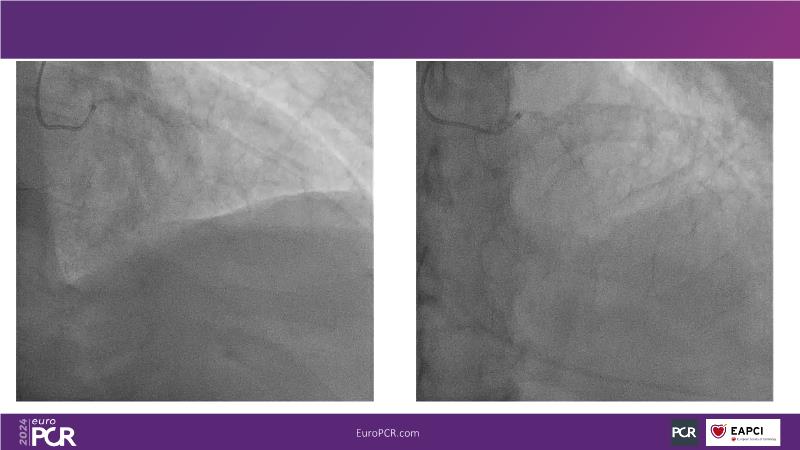

Tune in to this session to discover how reducing reliance on contrast opacification enhances procedural safety and enables more thorough revascularization in complex PCI scenarios. Learn that ultra-low contrast (ULC) PCI encompasses various interventional skills and specialized tools, many already familiar to interventional cardiologists. Embrace a mindset shift, starting with applying ULC PCI principles in simple cases and progressing to complex interventions.

- To share the principles of PCI through recorded cases to better understand how they work in practice